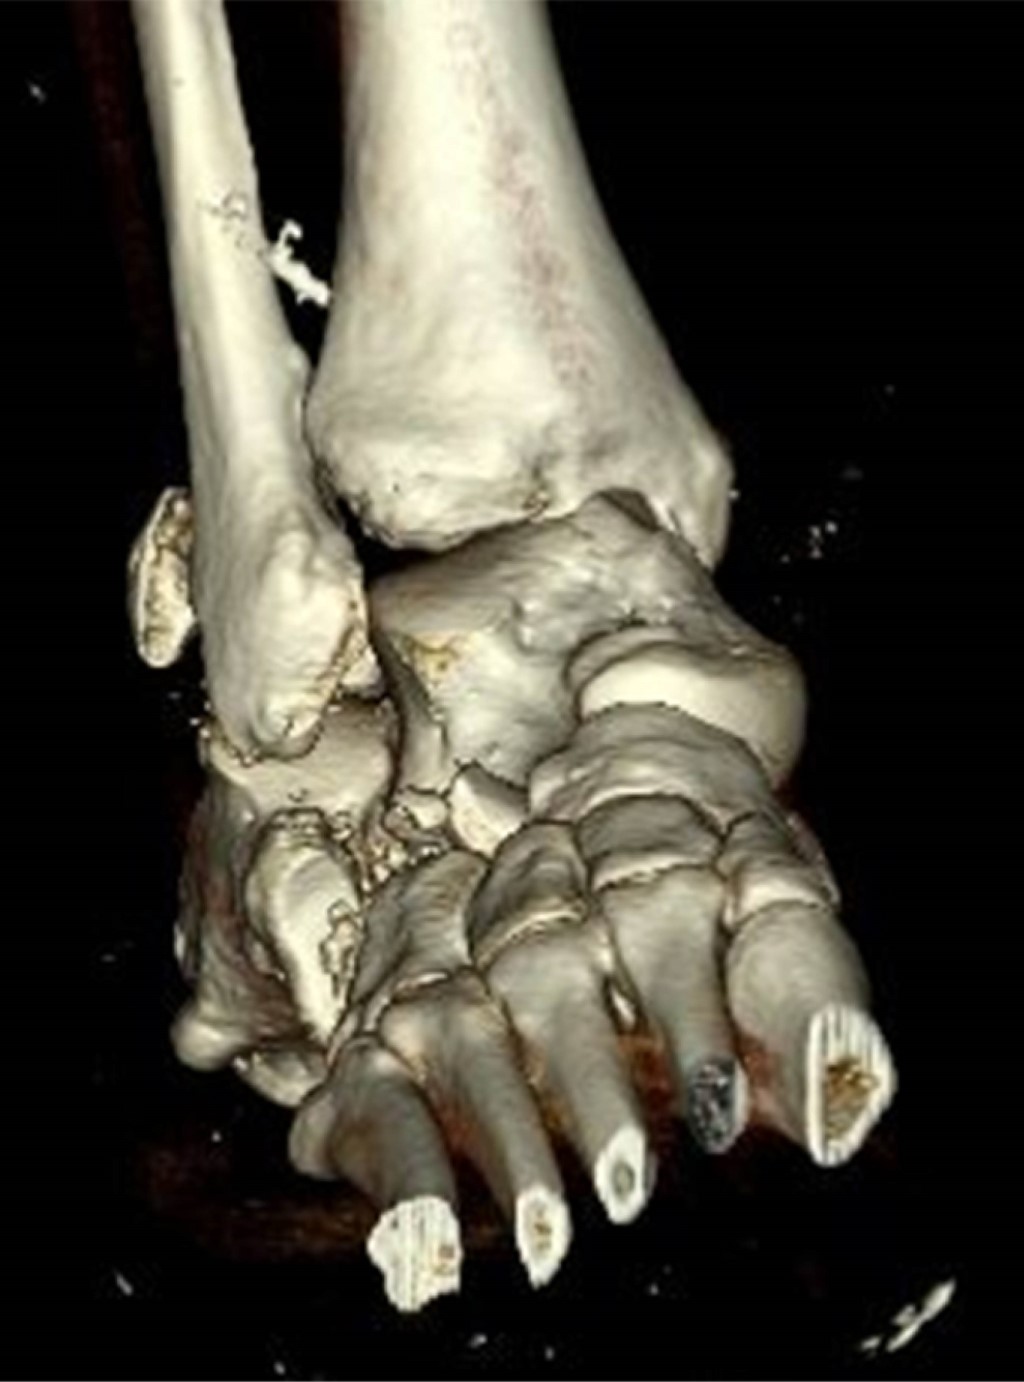

Irreductable lateral subatalar fracture-dislocation by entrapment of the posterior tibial neurovascular bundle: case report

Introduction: subtalar dislocations, typical of high-energy trauma, are classified as medial, lateral, anterior or posterior depending on the deviation of the foot in relation to the talus. Lateral dislocation accounts for 17% of the total and has a worse prognosis. Immediate reduction is required to reduce the risk of sequelae, the incidence of which is around 90%. Objective: a case of lateral subtalar dislocation is presented; a review of the literature on its diagnosis, treatment and prognosis is carried out. Clinical case: a 46-year-old woman fell from a height of 3 meters, with severe deformity in the hindfoot. There was good distal vascular coloration, but no pulse or posterior tibial sensitivity could be identified. In addition, she had a medial sulcocutaneous fold under the head of the talus. Plain radiograph and CT revealed lateral subtalar dislocation, with fracture of the sustentaculum tali, and a "fleck sign" in the posterior region of the distal fibula. Suspecting soft tissue incarceration, a medial approach was performed, observing interposition of the posterior tibial neurovascular bundle. After joint reduction, the sustentaculum tali and the "fleck sign" were osteosynthesized. In addition, a complete section of the long lateral peroneal tendon was identified, which was tenodesed to the short peroneal tendon. Finally, an external fixator was placed. After eight weeks, the fixator was removed and weight bearing was authorized; after six months, mobility was complete and hypoesthesia persisted only in the plantar pad. Conclusions: lateral subtalar dislocation is an uncommon entity with a poor prognosis. Adequate interpretation through a thorough examination and pre-reduction CT of the bone and soft tissue lesions minimizes future sequelae.